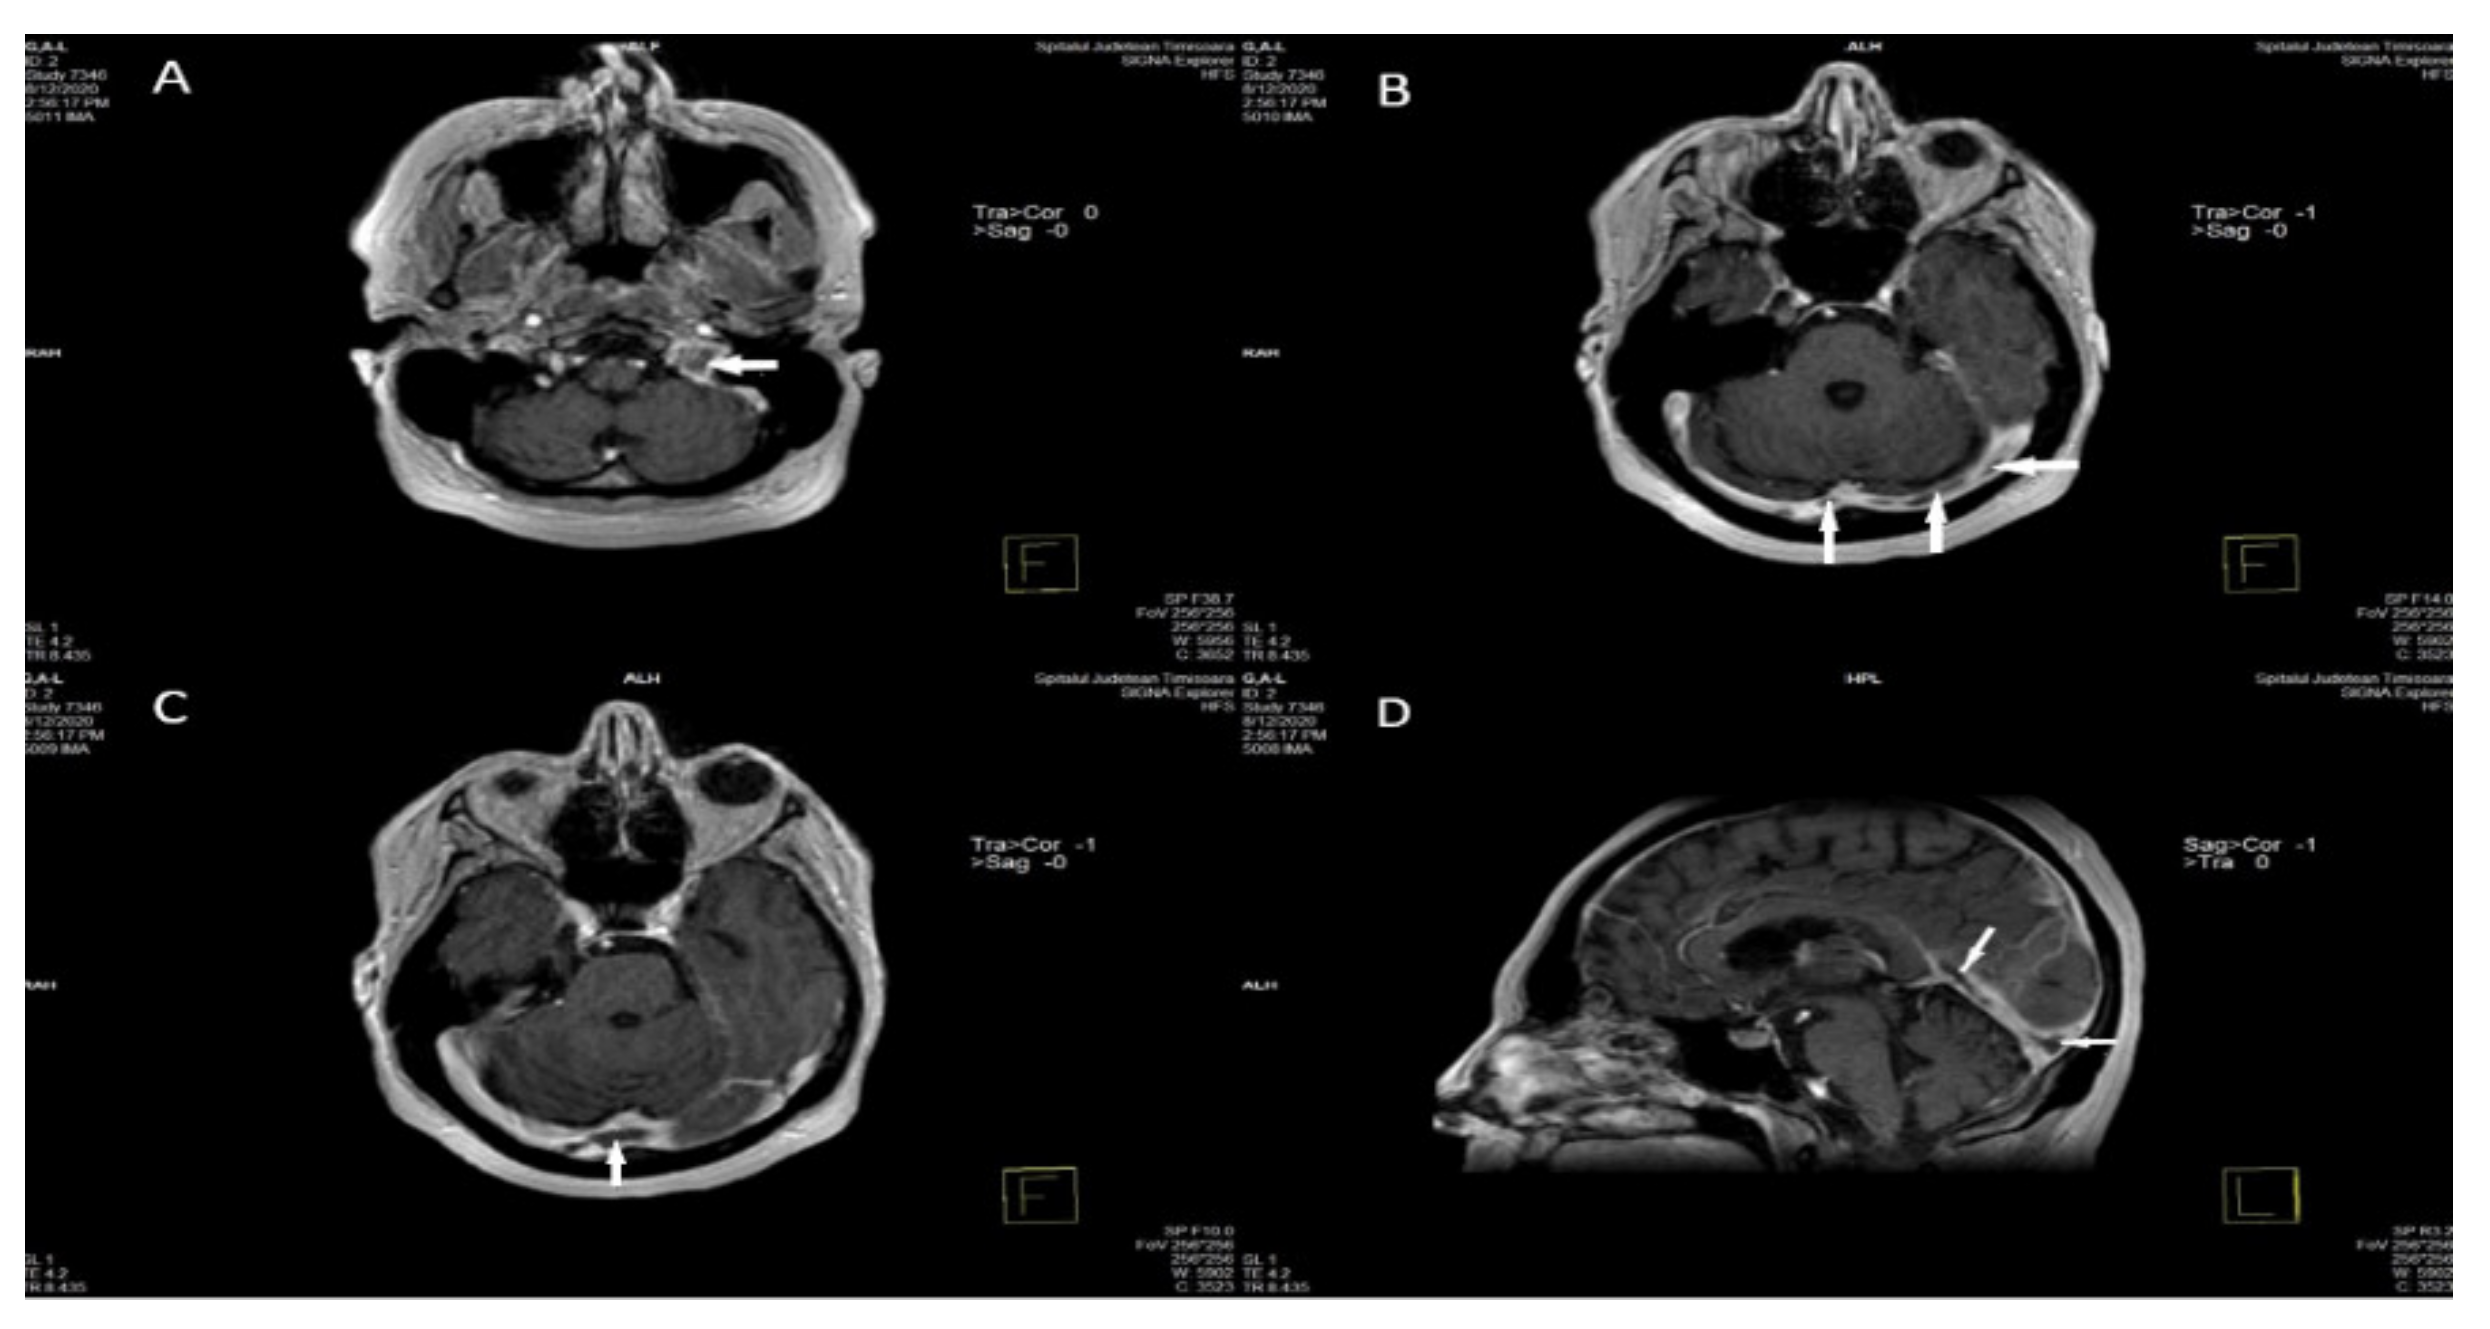

Acutely (0–5 days after the onset of the clinical aspects), flow void is missing and the thrombosed dural sinus or cerebral vein is isointense with brain tissue on T1-WI and hypointense on T2-WI, due to the abundance of deoxyhemoglobin in red cells within the clot. The detection of CVT in this phase is practically very difficult on MRI alone because the MRI aspect is similar to normal flow. For this reason, other MRI sequences, MRV, CTV, or cerebral intra-arterial angiography are needed to certify the absence of flow in the occluded venous channel [12,89,90] (Figure 4) [58].

Figure 4.

A, B, C, D. Axial and sagittal T1 post-contrast magnetic resonance demonstrate extensive filling defects throughout the dural sinuses (arrows-left sigmoid and jugular bulb (A), left and right transverse sinuses (B), sinus confluence (C), straight sinus (D)) [58].